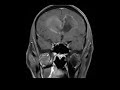

Glioblastoma

These images demonstrate a T1 isointense, T2 hyperintense peripherally enhancing mass with central necrosis which courses along the genu of the corpus callosum. On susceptibility we see decreased signal along the margins compatible with hemosiderin. These are imaging features of a high grade lesion which in this case turned out to be glioblastoma. This butterfly pattern is a characteristic pattern of spread for this lesion. Glioblastoma is the most common primary brain tumor in adults and has the worst prognosis. Peak incidence is between ages 65-75. Another tumor which has a propensity for crossing the corpus callosum is lymphoma which can have a variable appearance, but is usually hyperdense on CT and is isointense to hypointense on T2 weighted images.